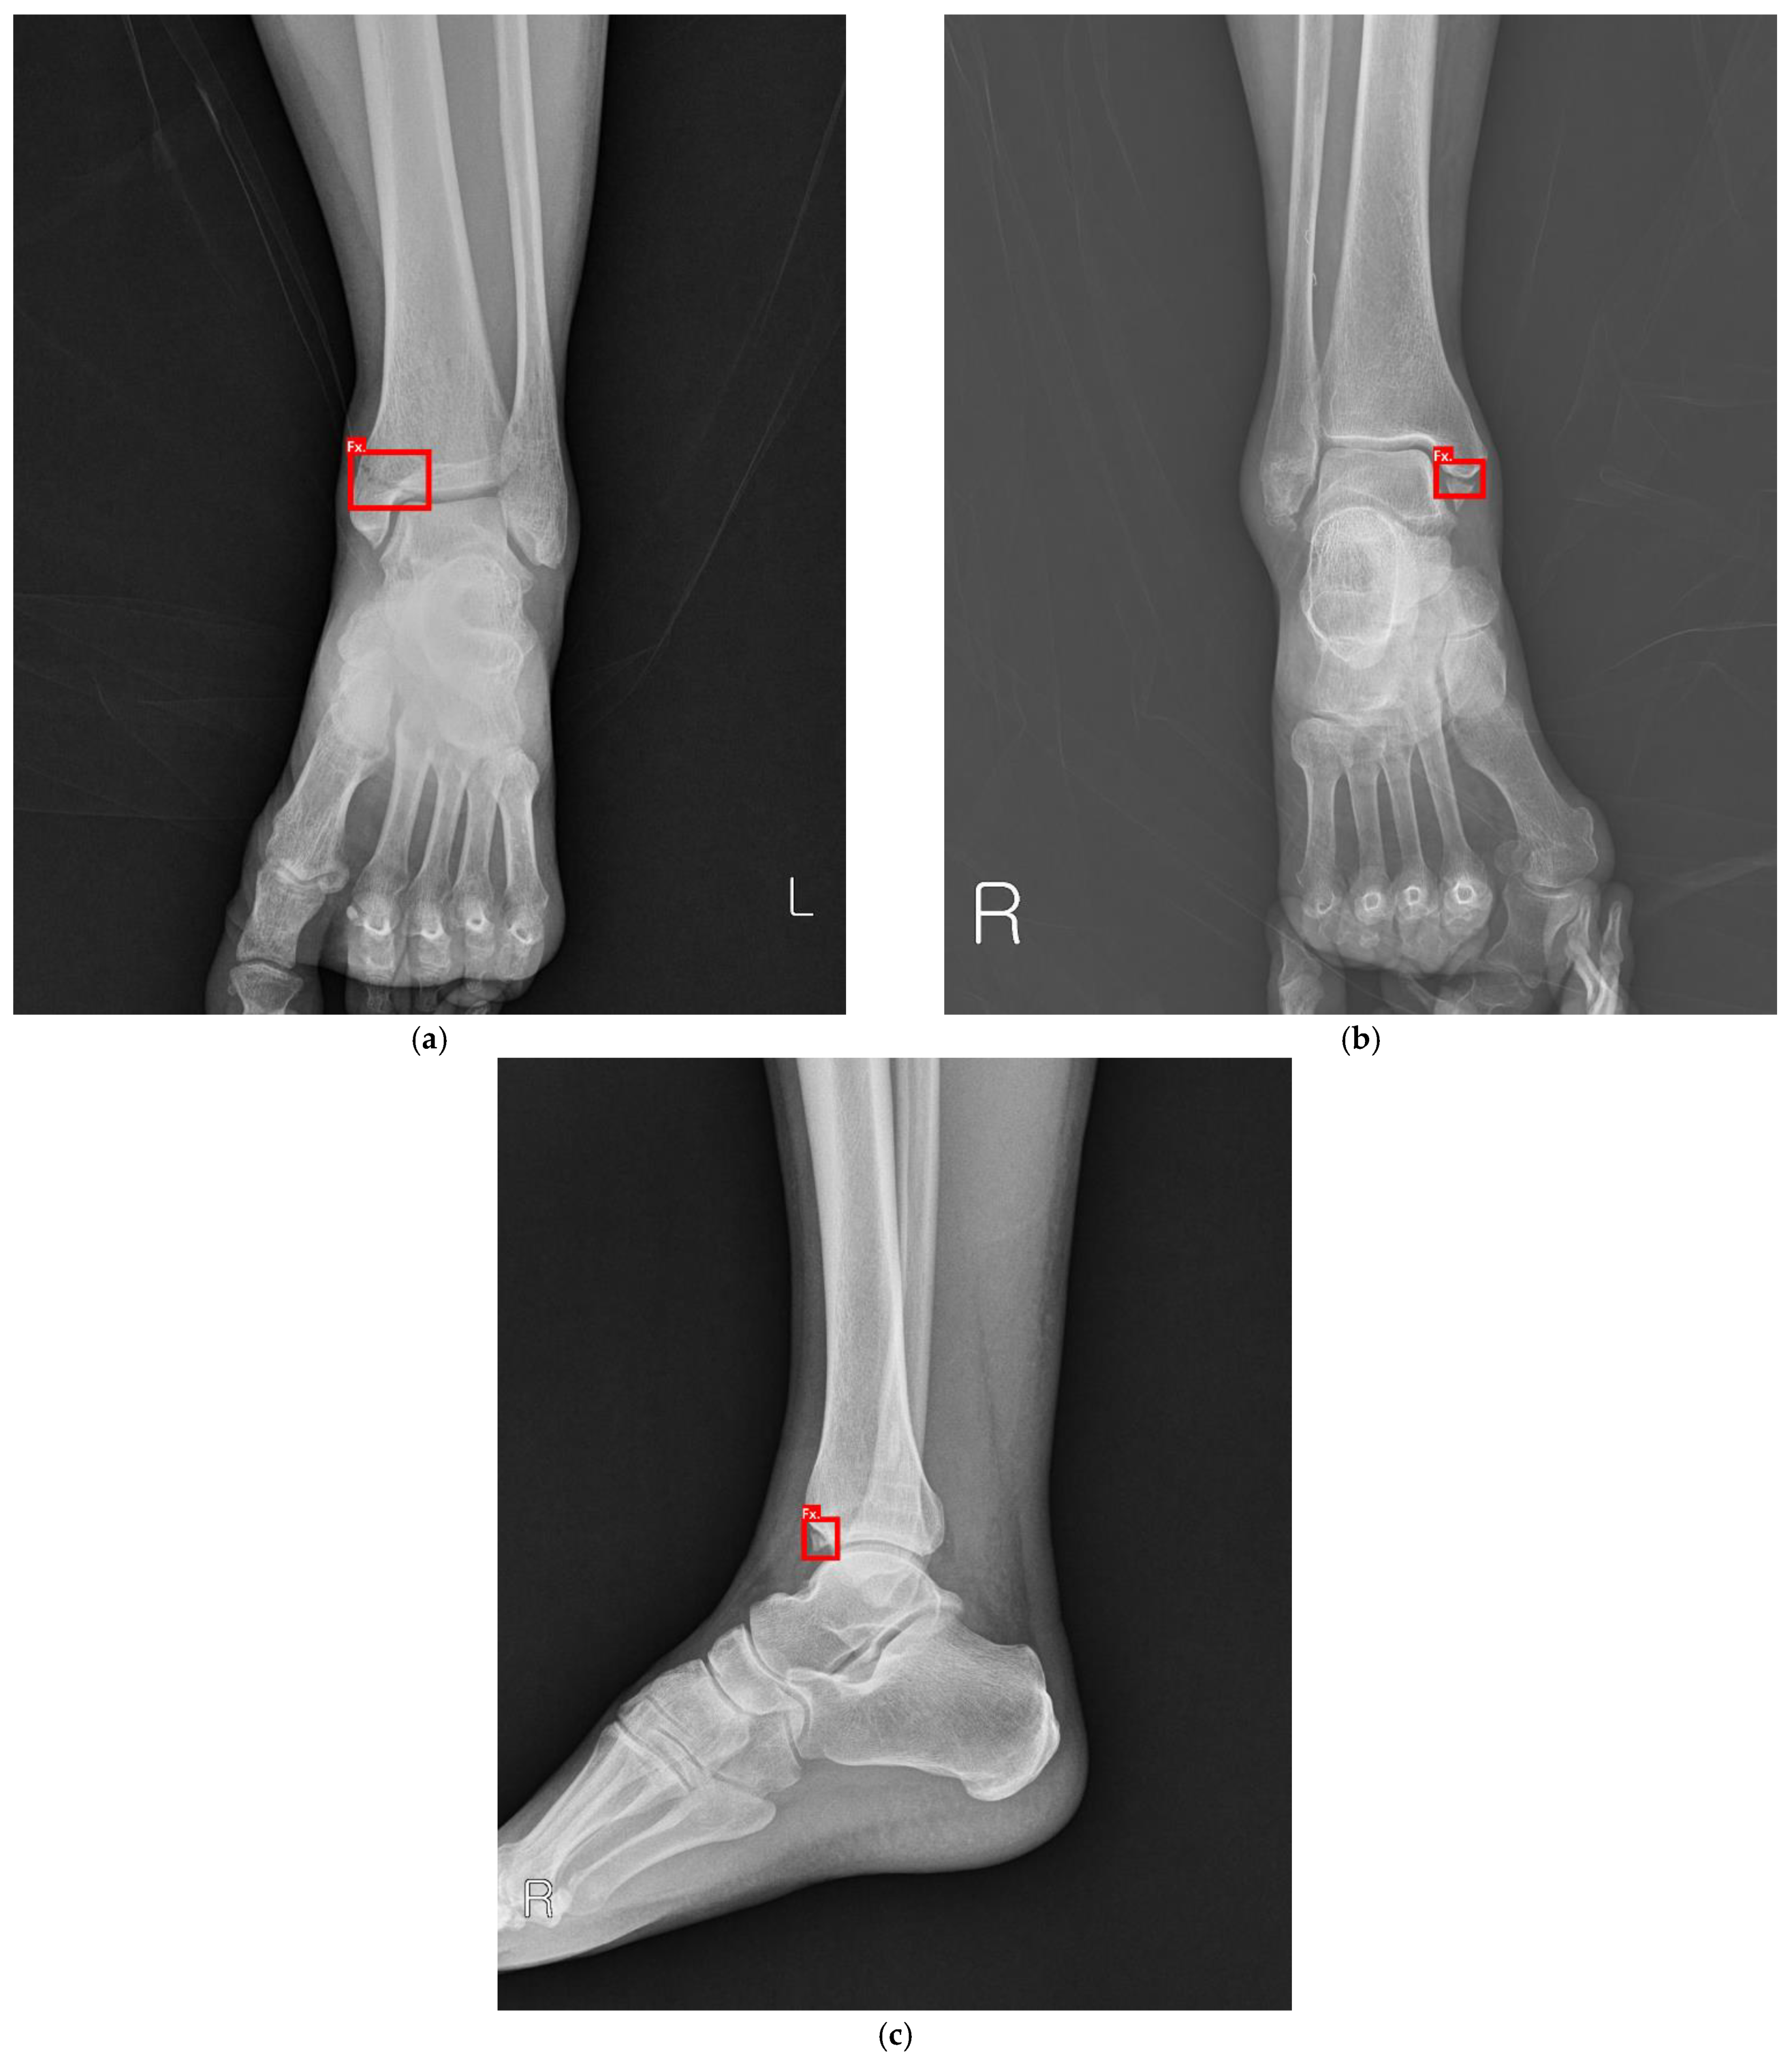

Detecting Ankle Fractures in Plain Radiographs Using Deep Learning with Accurately Labeled Datasets Aided by Computed Tomography: A Retrospective Observational Study

2.1.1. Dataset Preparation